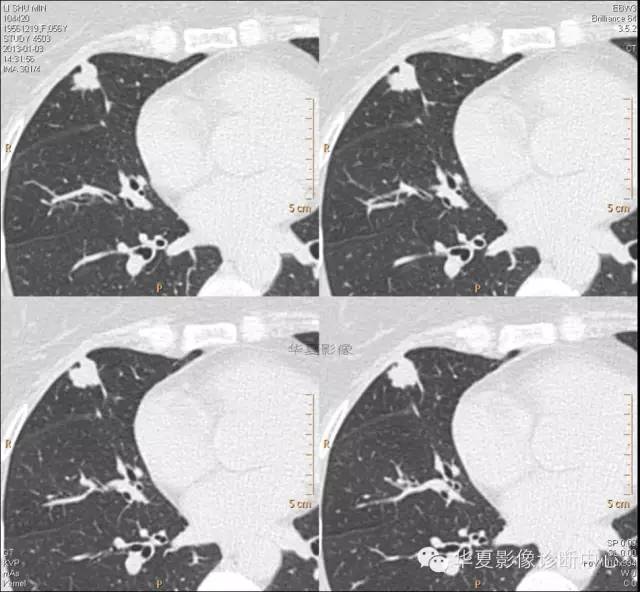

【病例学习】典型周围型肺癌CT病例一例

女,56岁,其父因肺癌去世,自觉胸部疼痛不适来诊要求拍胸片。

1.右肺上叶:肺组织1块,大小13×4×7cm。切面棕红色。2.右肺上叶肿物:灰白色组织一块,大小3×1×1.5cm。切面灰白色。3.右肺中叶结节:灰白色绿豆大组织1块。4.淋巴结:灰黑色绿豆大组织1块。

(右)肺中分化鳞状细胞癌。浸及胸膜。支气管残端切净。淋巴结未见癌转移(0/10)。